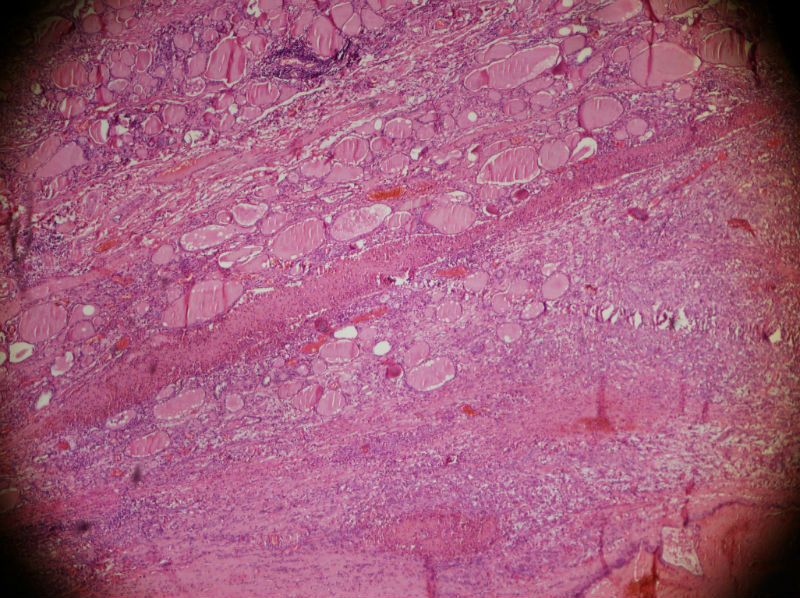

男,44,甲状腺囊肿.直径1.5公分,内流清亮液

结节性甲状腺肿伴囊性变

结节性甲状腺肿伴出血、囊性变。囊肿边上的滤泡大小不一,纤维组织增生,还可见炎细胞浸润。

结节性甲状腺肿伴囊性变。图2右上角的滤泡上皮似乎有些嗜酸性变。总之:良性病变。图13伴有出血。

结节性甲状腺肿伴囊性变。不知道有没有穿刺病史。

结节性甲状腺肿囊性变伴周围慢性炎细胞感染。